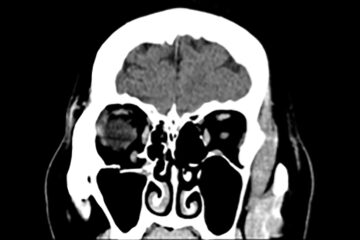

viability